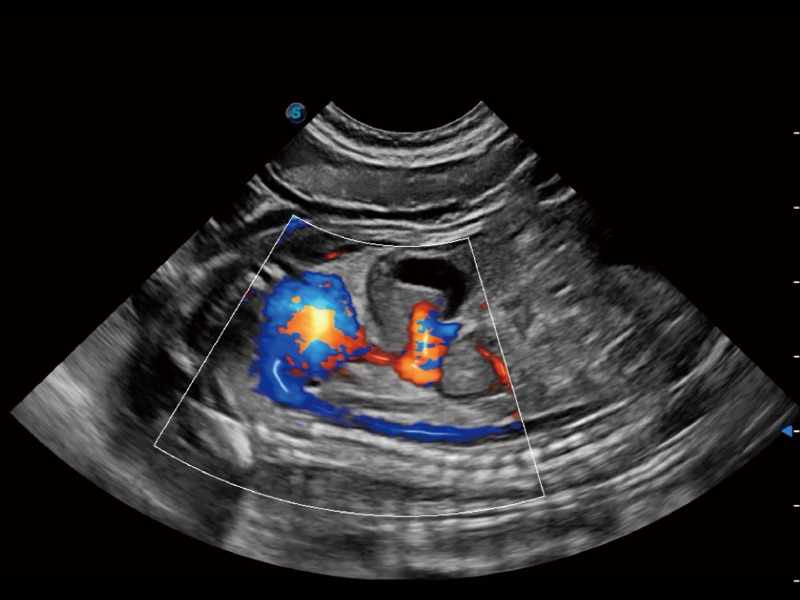

(犬)髂动脉血流

(犬)胎儿主动脉弓立体血流